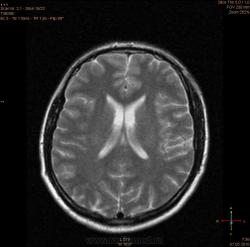

ID:56081

Болезнь Маркиафавы-Бигнами посмотри. На мой взгляд подходит.

Я заметил только 1 очаг в валике мозолистого тела. А для б-зни Маркиафавы-Бигнами более характерно несколько очагов дегенерации, в том числе и в полушариях.

По моему просто опухоль, м.б. глиобластома.

Для болезни Маркиафава-Биньями считается патогноманичным центральная дегенерация мозолистого тела.

"Болезнь Маркиафава-Биньями – Болезнь Маркиафава-Биньями (Marchiafava, Bignami)- синдром при хроническом алкоголизме: энцефалопатия в форме центрального некроза corp.callosum (иногда и других комиссур). "

Я не против, действительно м.б. "Болезнь Маркиафава-Биньями". Особенно если нет динамики.

Но диф. ряд должен быть с опухолью. И если есть негативная динамика, тогда больше похоже на то, что в моз.теле не дегенерация, а "плюс-ткань" - обьемное образование. За октябрь сканов нет?

К сожелению первое исследование проводил ни я, а моя коллега, но контроль был за мной. Уже при первом исследовании, опухолевую принадлежность можно взять под сомнение, по скольку, даже допустим возьмем глиобластому это злокачественная опухоль из глиального ряда, т.е. должен быть тумор+отек=масс-эффект, ни того и не другого нет, ко всему этому сама локализация это валик мозолистого тела, а ни гемисфера, компенсации ни должно быть ни какой, клиника должно быть молниеносной и нарастающей.

Ко всему выше перечисленному могу добавить, видимо мою коллегу сомнения гложили, она провела исследование с контрастированием и получила тот же результат.